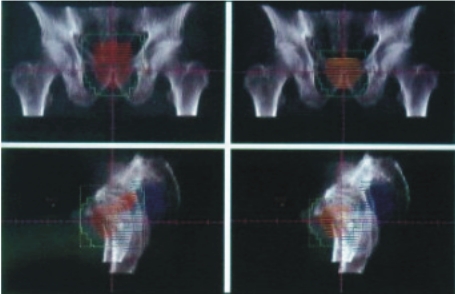

| 依腫瘤形狀製作屏蔽 |

影像取得 |

定位及確定角度 |

實際執行治療 |

所使用的治療方式是以三度空間的順形治療技術,即由電腦斷層或核磁共振影像,確定治療之標的物,且將影像輸入三度空間治療計劃系統,由此軟體之運算可決定最適合腫瘤形狀及大小之治療照野、治療角度及所需之治療附屬工具之使用機會,以幾近完美之劑量分佈涵蓋腫瘤所需治療之範圍。此外再搭配良好之體外固定系統(真空墊)以確定重覆治療之準確性。所有治療均可於門診實施。所使用腫瘤劑量為45~60葛雷(Gy),分次於5~6週進行(每天一次,每週五天)。